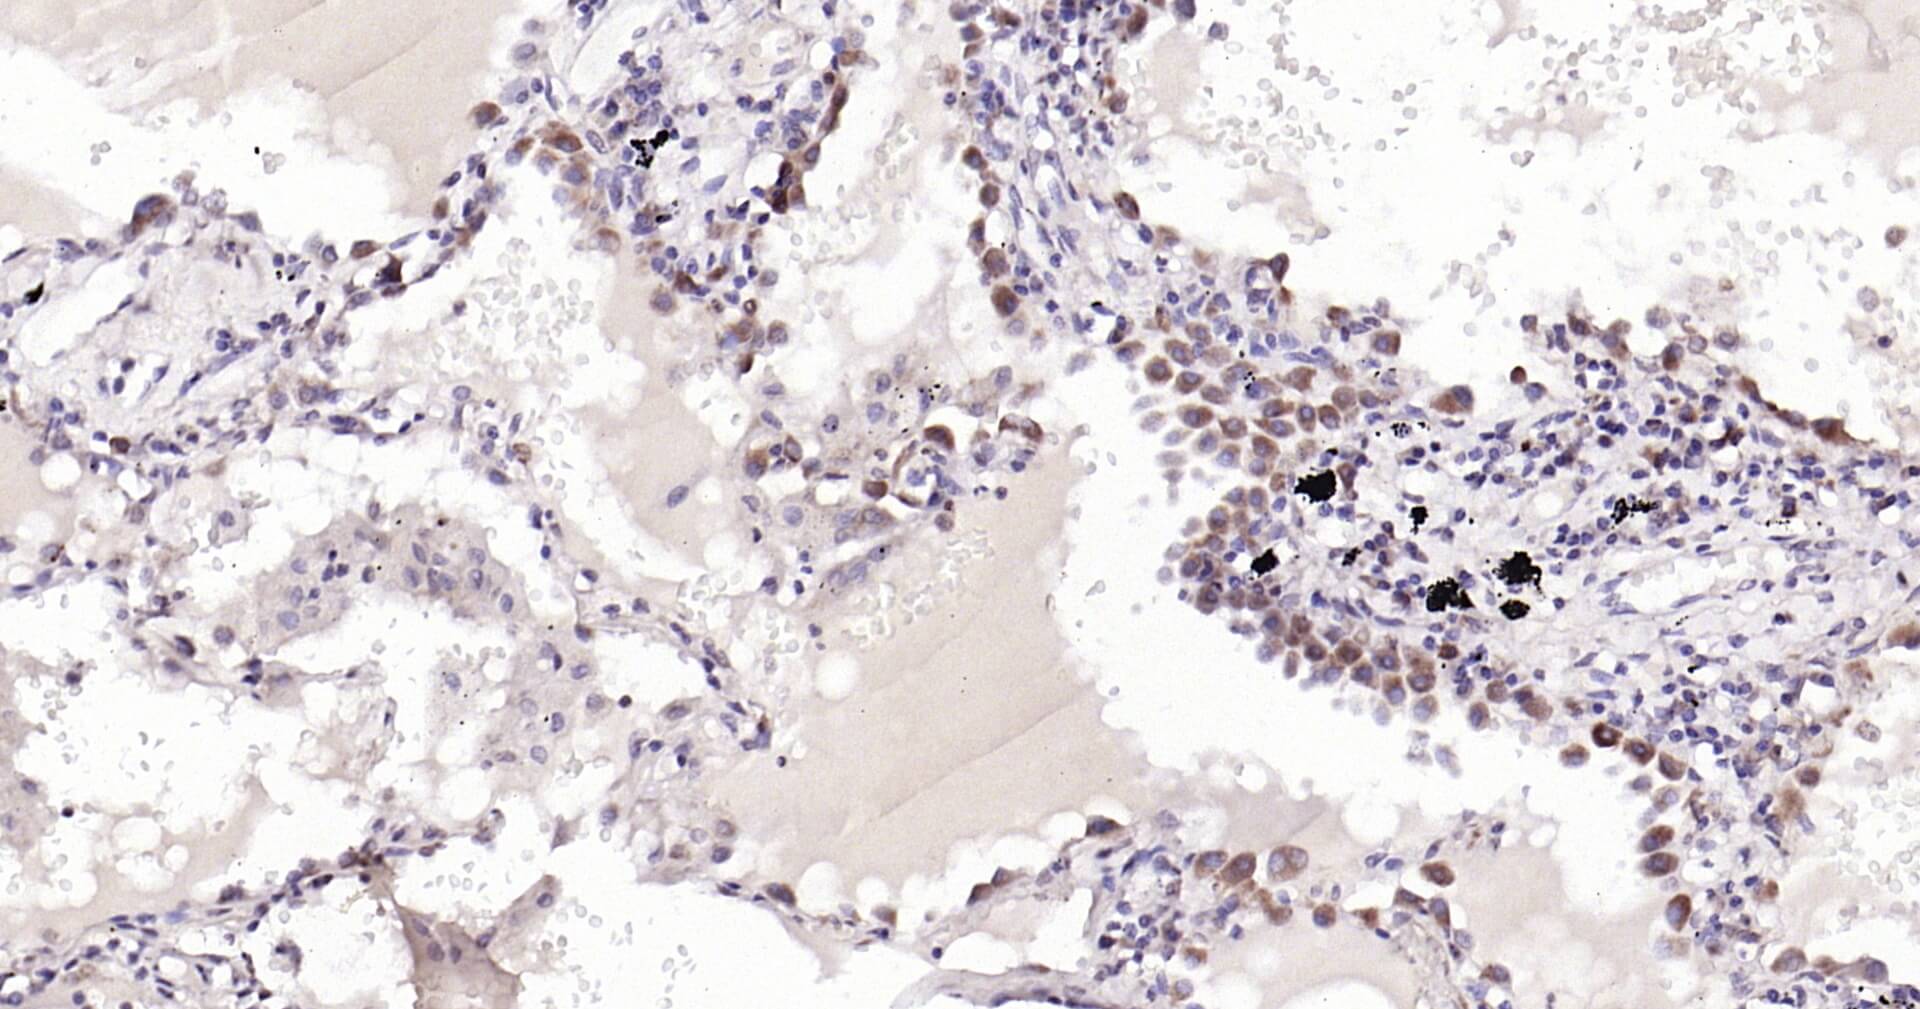

Immunohistochemical analysis of paraffin embedded human lung carcinoma tissue slide using IHC0117H (Human Cytochrome C IHC Kit).

描述 IHC0117H is a ready-to-use IHC kit for staining of human Cytochrome C. The kit provides all reagents, from antigen retrieval to cover slip mounting, that require little to no diluting or handling prior to use. Simply apply the reagents to your sample slide according to the protocol and you're steps away from obtaining high-quality IHC data. Cytochrome C is an electron transporting protein that resides within the intermembrane space of the mitochondria, where it plays a critical role in the process of oxidative phosphorylation and production of cellular ATP. An increasing amount of interest has

產(chǎn)品介紹 Cytochrome C is an electron transporting protein that resides within the intermembrane space of the mitochondria, where it plays a critical role in the process of oxidative phosphorylation and production of cellular ATP. An increasing amount of interest has been directed toward the role which cytocrome C has been demonstrated to play in apoptotic processes. Following exposure to apoptotic stimuli, cytochrome C is rapidly released from the mitochondria into the cytosol, an event which may be required for the completion of apoptosis in some systems. Cytosolic cytochrome C functions in the activation of caspase 4, an ICE family molecule that is a key effector of apoptosis.